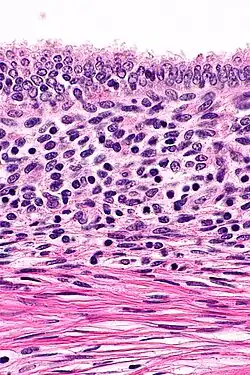

On microscopic examination, patterns of smooth muscle and endometrial tissue must be assessed with care to differentiate adenomyomas from masses of similar appearances, such as endometriosis containing smooth muscle and leiomyomas containing endometriosis.[3]